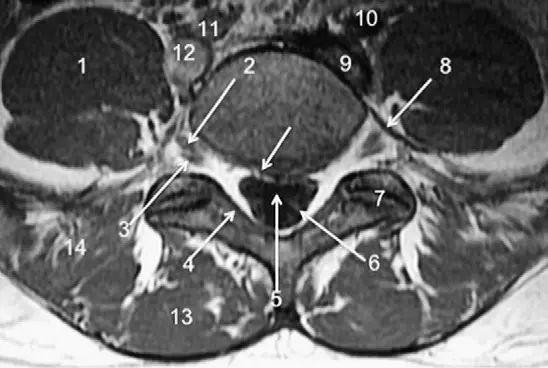

图 4 L5/S1 水平轴位 T1WI 序列成像:1,腰肌;2,L5 神经根(前支);3,L5 神经根(后支);4,黄韧带;5,蛛网膜下腔;6,马尾神经根;7,小关节面;8,髂腰韧带;9,左髂外静脉;10,左髂外动脉;11,右髂外动脉;12,右髂外静脉;13,多裂肌;14,竖脊肌组